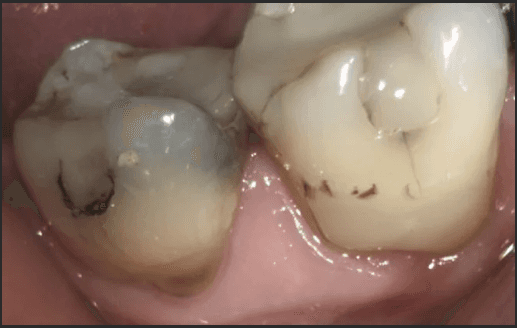

We take replacing amalgams very seriously. We take every precaution necessary to minimise any mercury exposure not only for you, but also for us. The precautions we take are outlined by the International Academy of Oral Medicine and Toxicology (IAOMT) called the Safe Amalgam Replacement Removal Technique (SMART).

Upon taking the necessary SMART precautions to remove the amalgam as safe as possible, there was considerable amalgam remaining, as well as secondary decay.